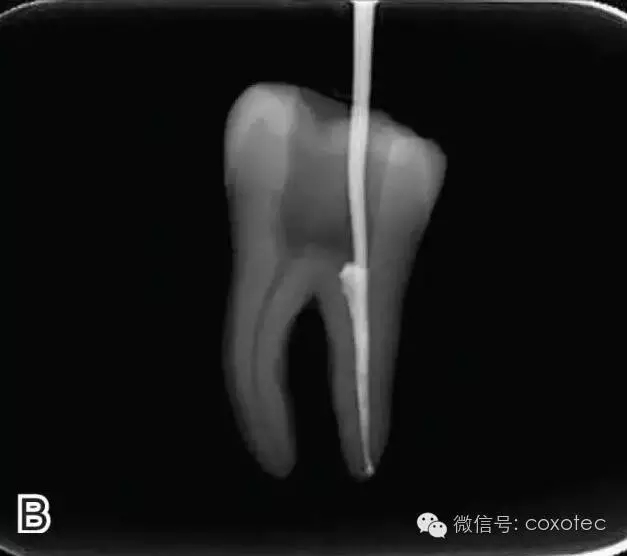

將主尖的尖1/3 部分蘸一薄層根充糊劑,緩慢插入根管內(nèi),并左右旋轉(zhuǎn)主尖,以將根充糊劑均勻涂布于根管壁上,如圖4所示。

圖4 放置主尖及糊劑,A.放置主尖及糊劑 B.X線片下示主尖及糊劑的放置